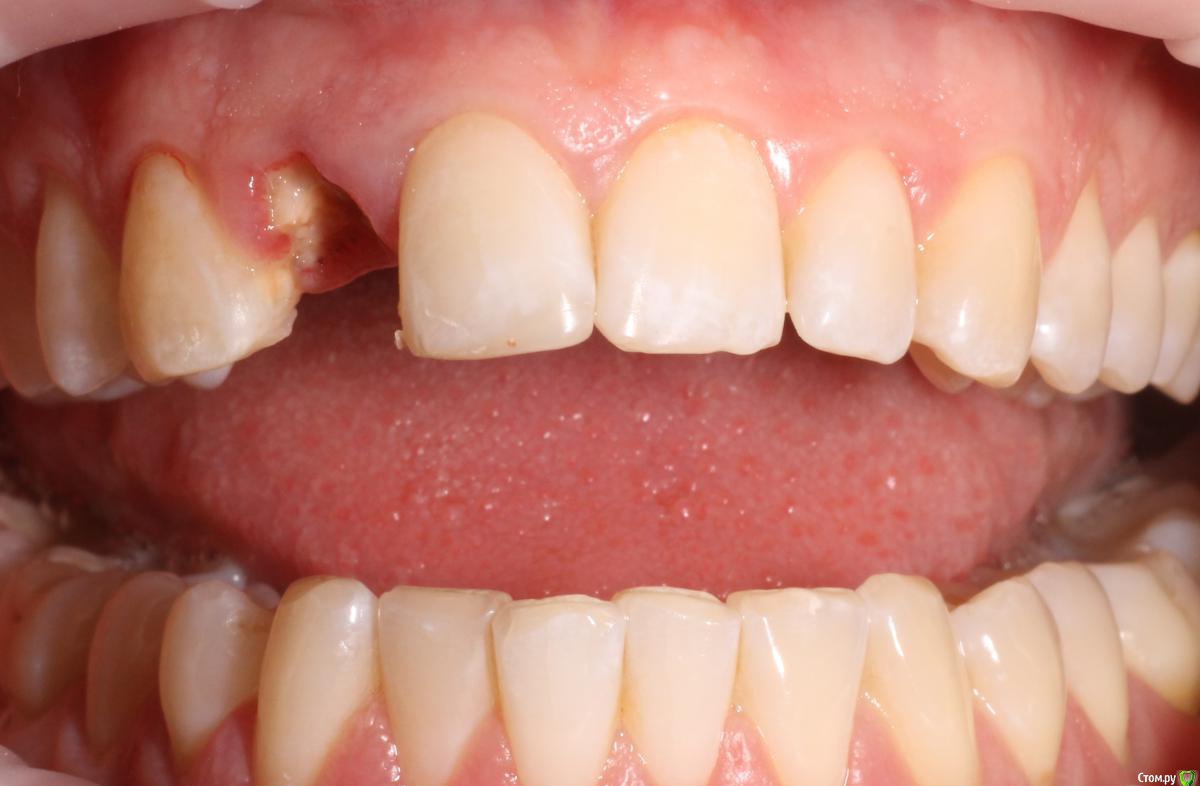

MenshikovDV Опубликовано 2 апреля, 2015 Поделиться Опубликовано 2 апреля, 2015 (изменено) Зуб 1.2 отлом коронковой части зуба, на период ожидания приема у хирурга и ортопеда (2 дня) приклеен к соседям. Вся процедура в одно посещение. Где-то часа два. Я ортопед, хирургия не моя, фото мои Изменено 2 апреля, 2015 пользователем MenshikovDV 19 Ссылка на комментарий

Brigita Опубликовано 5 апреля, 2015 Поделиться Опубликовано 5 апреля, 2015 на удаленном зубе какая то железячка хвостиком торчит))) Ссылка на комментарий

MenshikovDV Опубликовано 7 апреля, 2015 Автор Поделиться Опубликовано 7 апреля, 2015 ИНСТРУМЕНТ сломан в канале )) Ссылка на комментарий